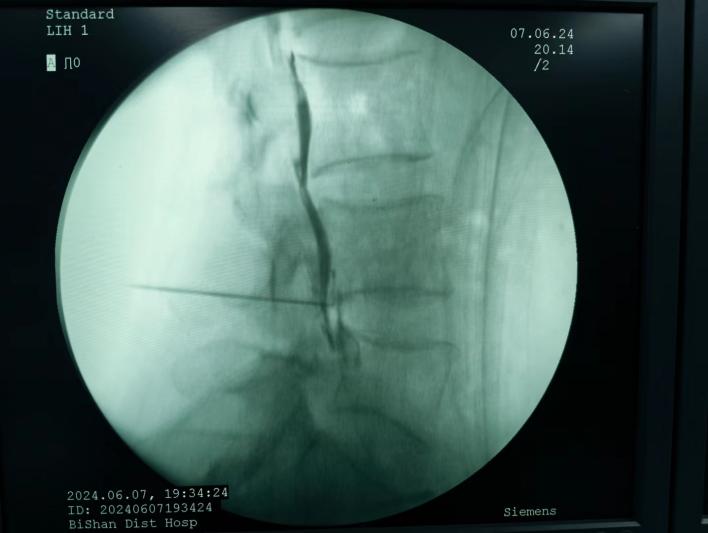

射頻消融治療,連續(xù)射頻或脈沖射頻對椎間盤或神經(jīng)進(jìn)行干預(yù)治療,目的是減小神經(jīng)根周圍的壓力及對神經(jīng)的調(diào)控治療,從而達(dá)到緩解癥狀的效果;

椎間盤射頻消融術(shù)、膠原酶椎間盤化學(xué)消融術(shù)